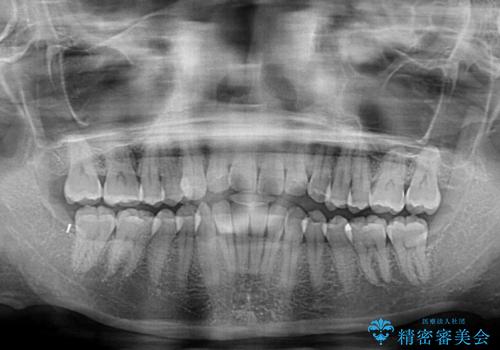

- 上下前歯の叢生を気にして来院された患者様です。

インビザラインでの治療を希望されていて、デコボコの程度が中等度であり、安価なパッケージにて対応可能と判断されたため、インビザライン・モデレートを用いて矯正治療を行うこととしました。